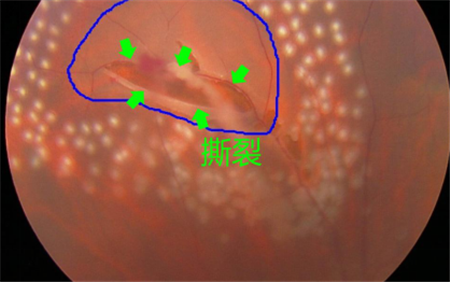

例如,對于視網膜撕裂引起的飛蚊癥,就需要對視網膜撕裂進行治療,通過激光將裂孔周圍進行燒焊凝固,以避免積水擴散造成嚴重的視網膜脫落;若飛蚊癥是由葡萄膜炎所致,就需要及時治療葡萄膜炎;對于糖尿眼導致的玻璃體出血,則需要通過激光治療以減少或避免增生血管的產生。